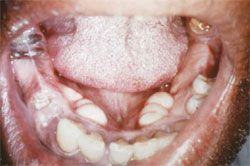

Woman who appears stated age. Vital signs and general examination, normal. Facial skin shows some telangiectases and lips have some wrinkling, suggesting solar damage. Nares unremarkable. Dorsum of tongue, normal. Anterior palate as shown.

A smooth mass juts down from the hard palate centrally or just barely to the left of the midline. It appears to be covered by smooth mucosa without ulcer or exudate. Two minute grooves or lobulations are seen on its left-hand surface.

On palpation the mass was bony hard beneath apparently normal mucosa. The combination is diagnostic of torus palatinus, a common variant of bony overgrowth at the palatine suture that is nonpathological.1,2 If the word torus feels half-familiar, it is from geometry, in which it refers to a doughnut shape. Somehow in anatomy this became transmogrified to a bump or protuberance.